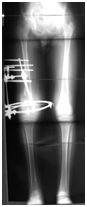

Figure 3 Application of Ilizarov frame in case 1.